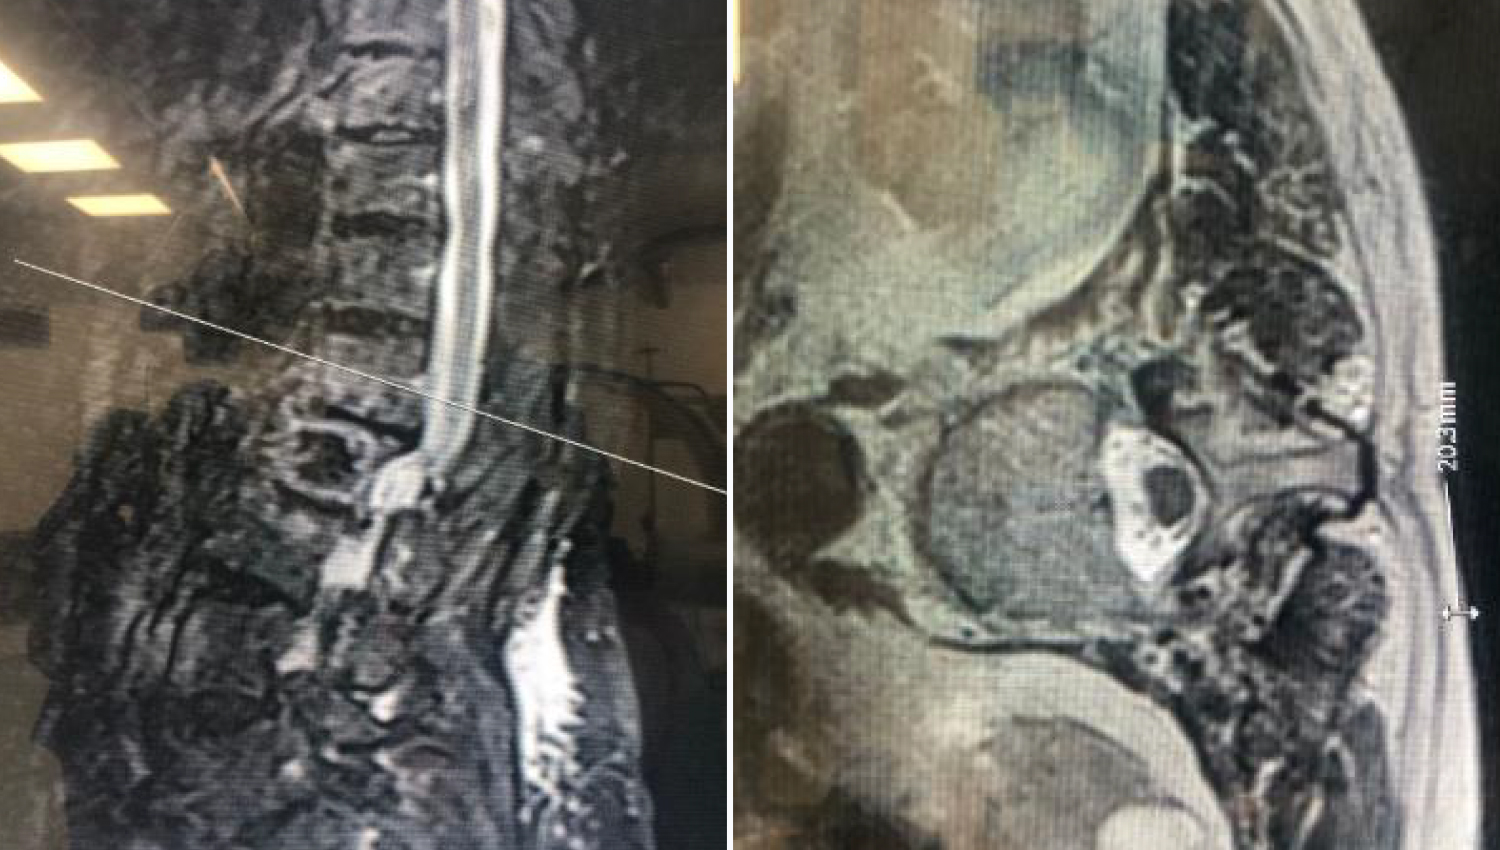

• There are osteophytic degenerative changes in the vertebral corpus corners and unsignaled areas of the therapeutic material in the L2 vertebral corpus, which may be due to previous surgery. It was decided to apply the Powerbone Bone Cement LV20.

1.Initial radiological view.